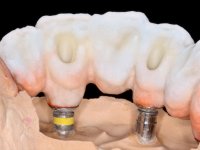

O paciente foi observado conjuntamente e a dúvida que surgiu de imediato foi se seria possível com a regeneração óssea a efectuar poder ser reabilitada naturalmente a zona das papilas interdentárias. Nesse sentido foi feito um enceramento de diagnóstico que contemplaria as duas hipóteses, utilizando ou não a cerâmica gengival. A confecção desse enceramento foi fundamental para expor ao paciente a dificuldade da reabilitação. O wax-up deu origem a um mock-up que foi aprovado pelo paciente e que simultaneamente serviu de guia imagiológica. O caso foi planificado cirurgicamente e realizada uma guia cirúrgica com que foram colocados os implantes. Após 10 semanas foi feita a 1ª impressão para confecção da ponte provisória. Foram criados os primeiros perfis de emergência na gengiva artificial e foi digitalizado o modelo. Por processo de CAD-CAM foi confeccionada uma ponte provisória aparafusada baseada no enceramento de diagnóstico. A ponte trabalhou durante 8 semanas os tecidos moles que foram fielmente copiados numa impressão com técnica de moldeira aberta. Os transferes foram individualizados com resina composta para copiarem fielmente os perfis de emergência criados pela ponte provisória. Confeccionado o modelo de trabalho definitivo, foi realizada uma infra-estrutura em zircónio seguindo a orientação do enceramento de diagnóstico. O assentamento da infra-estrutura foi testado em boca e simultaneamente foi novamente impressionados os tecidos moles com um silicone fluido. Nessa consulta foi feito o levantamento da cor. Os dentes 13 e 23 apresentavam uma saturação anormalmente forte que resolvemos não valorizar, optando por privilegiar a relação com o sector antero-inferior. Foi realizada uma nova gengiva artificial com a impressão que acompanhou a impressão de arrasto com a infra-estrutura. Após a colocação da cerâmica na infra-estrutura foram coladas as meso-estruturas. O trabalho final foi aparafusado lentamente permitindo a adaptação dos tecidos moles.